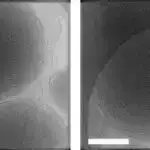

AMPA reseptorlarının (tək atomlar səviyyəsində) kiçik hərəkətlərinin təfərrüatlarını anlamaq üçün tədqiqatçılar rabitə proseslərində xüsusi addımlar zamanı bu kanalları təsvir etmək üçün çox güclü mikroskopdan istifadə etdilər. Tədqiqat üçün alimlər Johns Hopkins Universiteti Tibb Fakültəsinin bir müəssisəsində krio-elektron mikroskopdan (kriyo-EM) istifadə ediblər.

Bu məqsədlə alimlər laboratoriyada yetişdirilmiş insan embrion hüceyrələrindən götürülmüş AMPA reseptorlarını təmizlədilər və bu cür zülalları istehsal etmək üçün nevrologiya tədqiqatlarında geniş istifadə olunurlar. Sonra reseptorları glutamata məruz qoymadan əvvəl bədən istiliyinə (37 dərəcə Selsi və ya 98,6 dərəcə Fahrenheit) qızdırdılar. Bundan dərhal sonra reseptorlar dondurulmuş və əsas siqnal molekulu olan glutamata bağlı AMPA reseptorlarının şəklini almaq üçün cryoEM ilə təhlil edilmişdir.

CryoEM ilə çəkilmiş bir milyondan çox şəkli birləşdirdikdən sonra komanda glutamat molekullarının kanalın qapısını açan və onun daha geniş şəkildə açılmasına imkan verən açar kimi fəaliyyət göstərdiyini aşkar etdi. Bu, AMPA reseptorunun glutamat ətrafında bağlanan qapaqlı quruluşu ilə baş verir , bu hərəkət aşağıdakı kanalı açır.